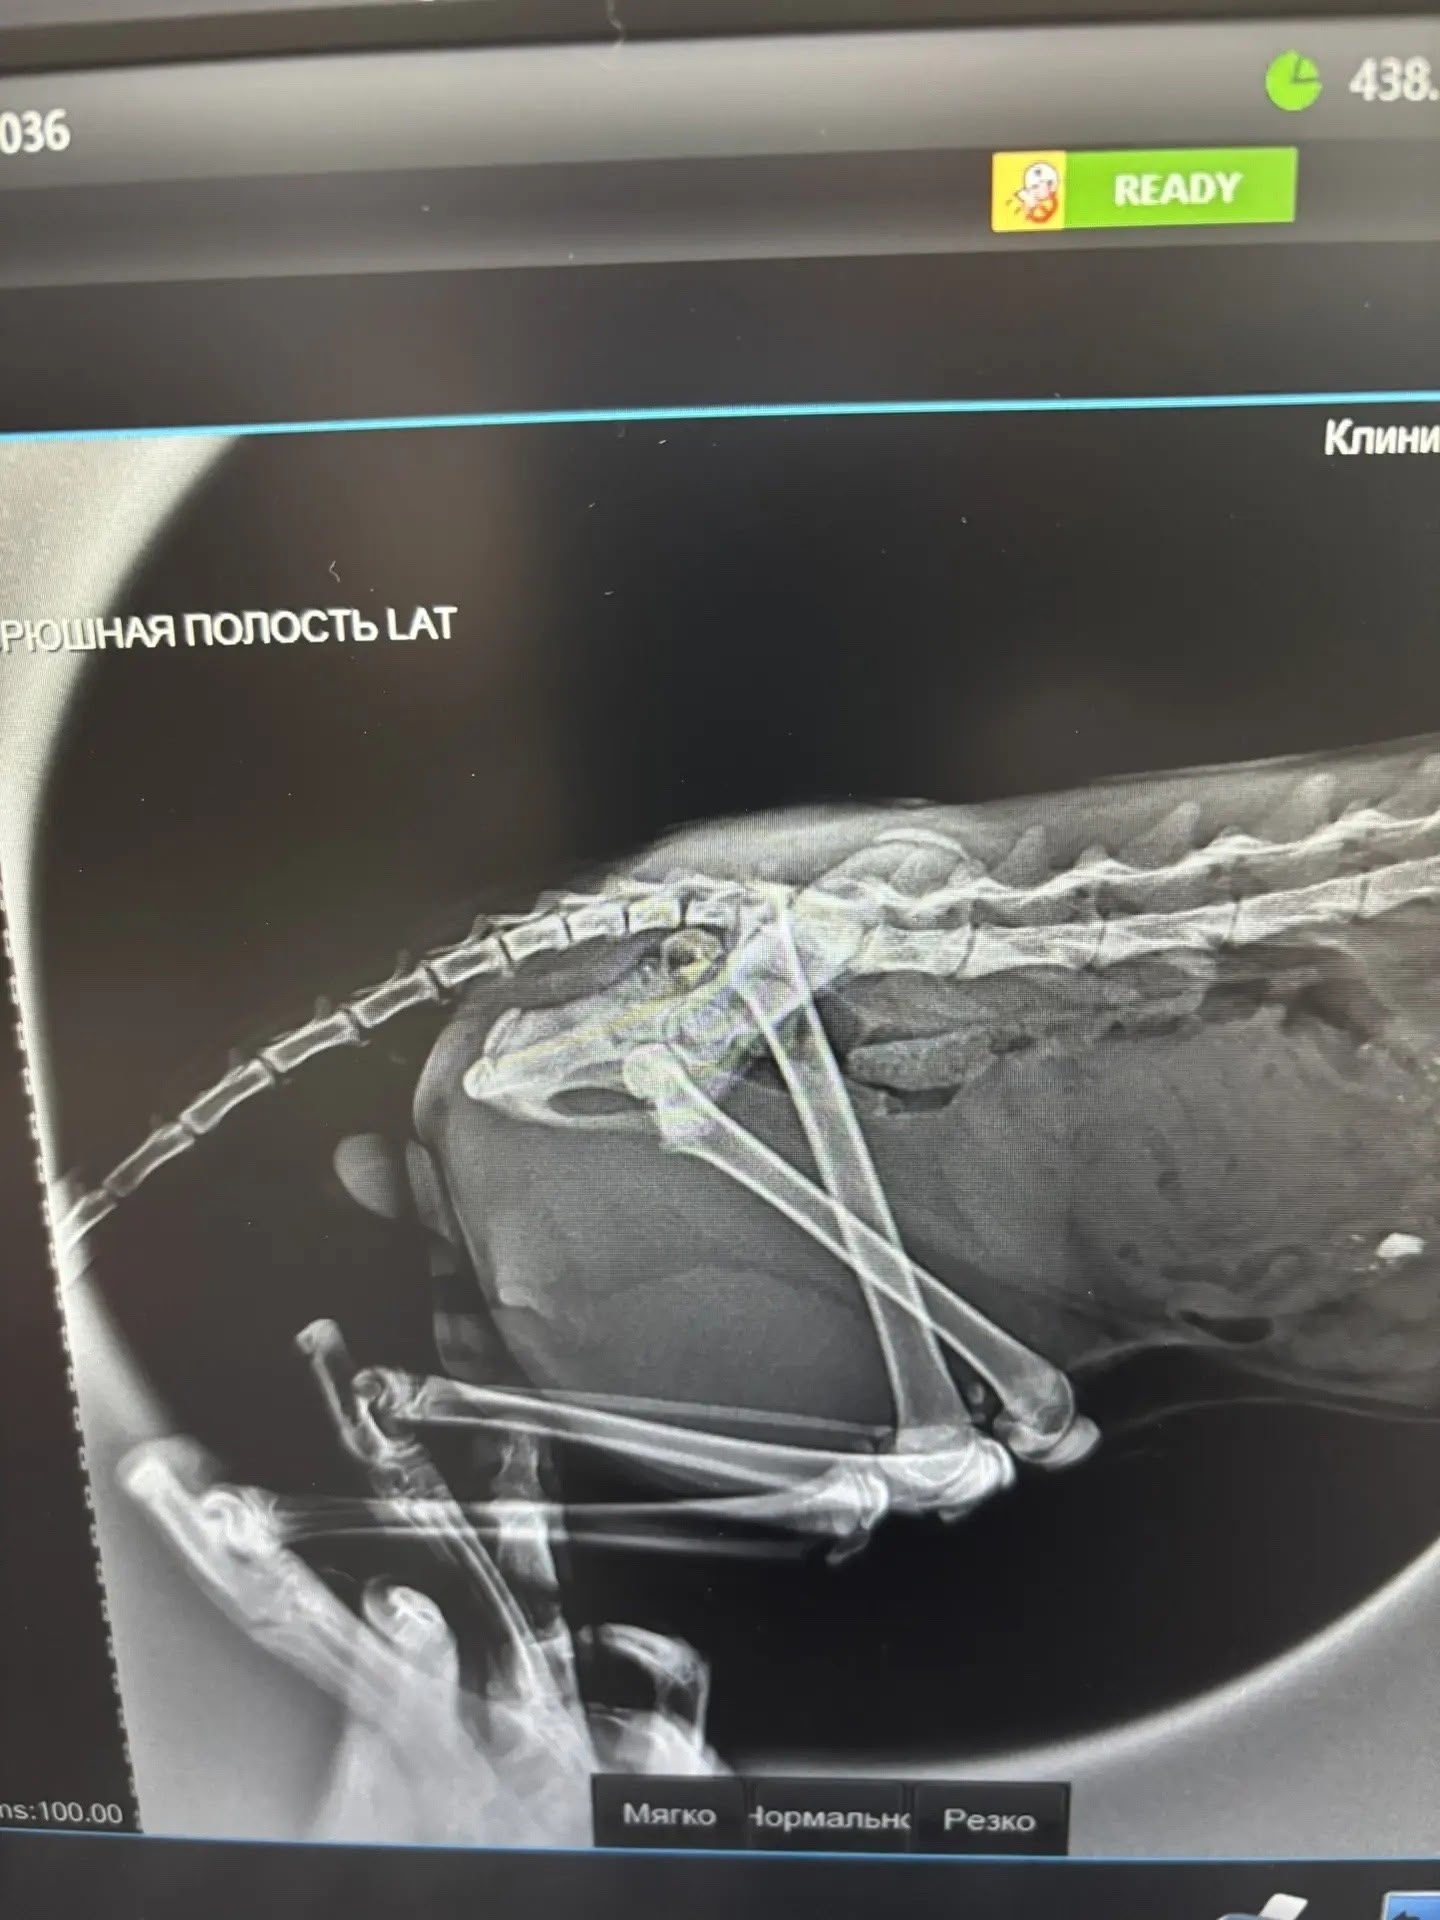

Вот у нас опять новенький с очень большой проблемой со здоровьем! Несколько дней кот лежал на одном месте (район школы N 9), даже невозможно представить сколько раз мимо проходили люди и всем было все равно! Равнодушие- страшное и такое современное слово! Его заметила женщина, кормила и поняла, что кот болен, забрала себе, но, к сожалению, финансово ей не осилить такие расходы и было принято решение забрать котика в приют. Назвали Дым, котик очень ласковый и есть маленькая надежда, но что он- потеряшка. Сдали анализы, сделали рентген- перелом шейки бедренной кости. Есть шанс встать котику на лапы, но для этого нужна огромная для приюта сумма -11 000 рублей, а еще анализы и рентген - 8 600, а у нас еще не закрыт сбор на стерилизацию Чернышки и куча финансовых расходов каждый день! Ну вот закидайте нас помидорами, но мы не могли поступить иначе! Операция уже 1 мая и осталось буквально несколько дней, и мы боимся, что не успеем собрать нужную сумму и котик Дым, возможно, уже никогда не встанет на лапки, если мы не успеем! Помогите нам, пожалуйста! Без вашей помощи Дым навсегда останется инвалидном без шансов найти дом!